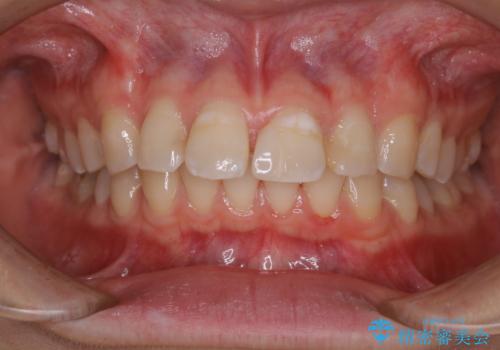

インビザラインで矯正治療を始める前にクリーニング

- これからインビザラインでのマウスピース矯正が始まるので、歯石取りをしてほしいとのことでした。

PMTC60分コースを行いました。

プラーク(細菌の塊)や歯石がたまると歯の表面はザラつきいてきます。そのザラつきは歯周病や虫歯菌の棲家となります。そのまま放置すると、歯肉が腫れてきたり、歯肉から出血したり、口臭が強くでたりします。とくに歯肉の境目は、歯磨きで汚れを除去することが難しく、プラーク(細菌の塊)や歯石が溜まりやすい場所です。

歯並が、がたついている場合はなおさら汚れが溜まりやすいです。矯正治療前や矯正中、定期的にPMTCをすることで、矯正治療中の歯肉トラブルを防ぐことにつながります。